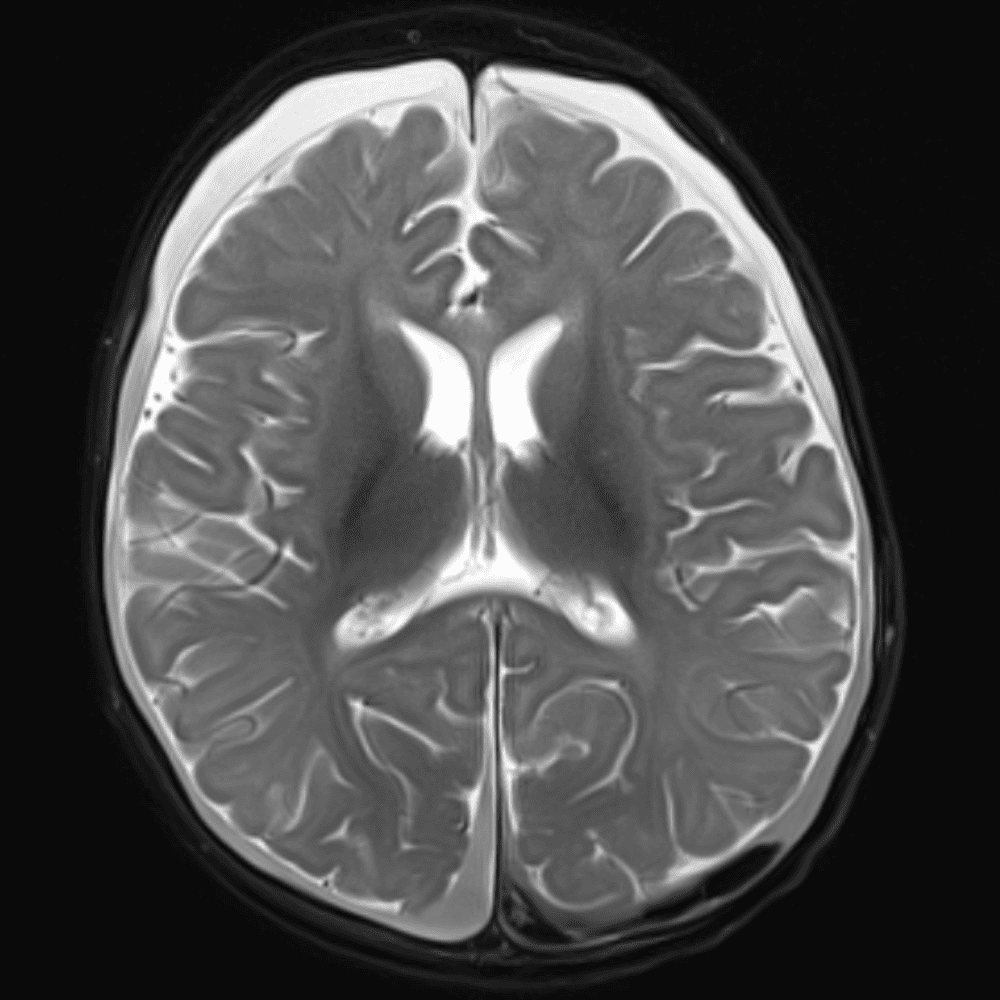

์—ฐ์Šต

๋ฏธ๋ฌ˜ํ•˜๊ฑฐ๋‚˜ ์–ด๋ ค์šด ์‚ฌ๋ก€์™€ ์ผ๋ถ€ ์ •์ƒ ์‚ฌ๋ก€๋ฅผ ํฌํ•จํ•˜์—ฌ ๋‹น์ง์„ ์‹œ๋ฎฌ๋ ˆ์ด์…˜ํ•ฉ๋‹ˆ๋‹ค.

50 ์‚ฌ๋ก€